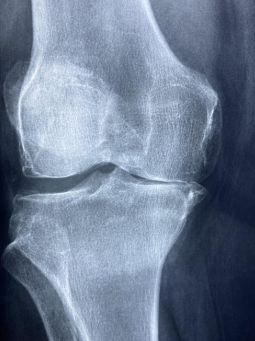

우리 몸의 관절은 나이가 들수록 약해집니다.

특히 40~50대 이후에는 무릎과 허리에 통증을 호소하는 사람이 많습니다.

관절은 뼈와 뼈를 연결하는 중요한 부분인데, 연골이 닳거나 염증이 생기면

일상생활이 불편해집니다.